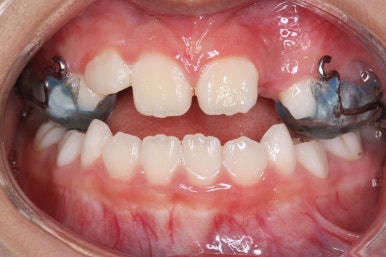

우선 처음 내원 하셨을 때의 입안의 상태를 보겠습니다.

아직 나이가 어리다 보니 곳곳에 유치가 남아 있었어요. 보통 이렇게 영구치가 다 나오지 않았을 경우, 보호자분들은 "치아교정"에 대해서는 전혀 생각해 보시지 않으셨을 수 있어요.

이번 환자분의 경우도 앞니가 거꾸로 물리는 상황이어서 치료가 필요한 상황이였습니다.

치료 시작 3개월째의 모습입니다.

윗니가 점점 앞으로 나오는게 보이실거에요. 사실은 치아가 나오는 것이 아니라 치아가 담겨있는 위턱뼈가 통째로 앞으로 나온 것입니다.